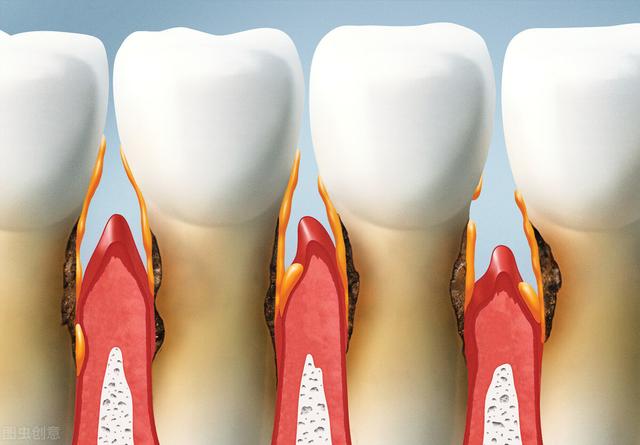

2、Ulzerativer oder exogener Typ: Zahnfleischkrebs kann sich klinisch als ulzerativer oder exogener Typ manifestieren, wobei der ulzerative Typ häufiger vorkommt. Der Beginn geht meist von den Interdentalpapillen und dem Zahnfleischrandbereich aus. Die Geschwüre sind oberflächlich und rötlich, und später kann eine Hyperplasie auftreten. Da das Mukoperiost und der Alveolarfortsatz sehr fest miteinander verbunden sind, ist es einfacher, das Periost und den Knochen des Alveolarfortsatzes in einem frühen Stadium anzugreifen, was zu einer Lockerung des Zahns führt, der dann möglicherweise abgetrennt wird.

3) Ausbreitung und Zerstörung: Unabhängig davon, ob der Zahnfleischkrebs von der bukkalen (Lippe) oder der palatinalen (Zunge) Seite ausgeht, kann er sich über den Interdentalraum auf die gegenüberliegende Seite ausbreiten; auf der Außenseite dringt jede Seite in den Lippen- und Wangensulkus ein, während auf der Innenseite jede Seite in den Mundboden und den Gaumen eindringt; nach oben hin kann er den Boden der Kieferhöhle zerstören, den Knochen durchdringen und in die obere Kieferhöhle eindringen, was zum sekundären Kieferhöhlenkrebs wird; nach unten hin kann er den Kieferknochen beeinträchtigen, und im fortgeschrittenen Stadium kommt es sogar zu einer pathologischen Fraktur. Nachdem der Zahnfleischkrebs in den Knochen eingedrungen ist, kann auf dem Röntgenbild eine unregelmäßige, wurmstichartige Resorption zu sehen sein, die das zerstörerische Merkmal des bösartigen Tumors ist.

Bei der Untersuchung der Frühsymptome von Zahnfleischkrebs können kleine Geschwüre am Zahnfleisch gefunden werden, die oberflächlich und hellrot sind, und später kann eine Hyperplasie auftreten, bei der kleine Papillen am Rand hervorstehen.Im Röntgenbild kann das zerstörerische Merkmal eines bösartigen Tumors erscheinen, eine wurmartige unregelmäßige Absorption. Spezifische Symptome sind wie folgt: 1, lange Zeit nicht heilende Geschwüre am Zahnfleisch, schnelle Vergrößerung, oder lange Zeit Wunde nach Zahnextraktion, Klumpen hervorstehen.2, Lockerung der Zähne und Schmerzen im Bereich der Läsion.3, wenn es entwickelt sich nach hinten zu hinteren Bereich der Backenzähne und Rachen, kann es Schwierigkeiten bei der Öffnung des Mundes verursachen, und wenn es den unteren Alveolarnerv betrifft, kann es Taubheit der Unterlippe verursachen.4, Vergrößerung der zervikalen Lymphknoten.5, Röntgen zeigt, dass Kieferknochen "fächerförmige" Knochen Zerstörung ist. Die Röntgenuntersuchung zeigt, dass der Kieferknochen "fächerförmig" zerstört ist, und der Rand ist wurmartig.6. Die pathologische und histologische Untersuchung bestätigt die Diagnose.

Die Frühsymptome von Zahnfleischkrebs äußern sich wie bei den meisten oralen Krebsarten in Form von Geschwüren, die in der Regel leicht mit Mundgeschwüren unter normalen Bedingungen verwechselt werden können. Frühsymptome von Zahnfleischkrebs treten meist im Oberkieferbereich auf, vor allem im Bereich der Backenzähne und der Frontzähne (um die Zähne des sechsten Lebensjahres herum). Die Frühsymptome sind gekennzeichnet durch eine nicht schmerzhafte, aber rasche Entwicklung, eine Verhärtung an der Basis und um die Geschwüre herum, und die Ränder der Geschwüre sind dachförmig erhöht, und dann kommt es zu einer blumenkohlartigen Veränderung an der Oberfläche.

Ein frühes Gingivakarzinom, insbesondere wenn es auf den Zahnfleischrand oder die Interdentalpapillen beschränkt ist, wird leicht als Gingivitis oder Parodontitis fehldiagnostiziert; zweitens können frühe ulzerative Läsionen, insbesondere diffuse Zahnfleischränder, die von Schmerzen begleitet sind, auch als Gingivatuberkulose fehldiagnostiziert werden. Bei der klinischen Diagnose der oben genannten Krankheiten sollte auf die Möglichkeit eines Gingivakarzinoms geachtet werden, und die Röntgenuntersuchung zeigt eine "fächerförmige" Zerstörung des Kieferknochens mit wurmartigen Rändern.